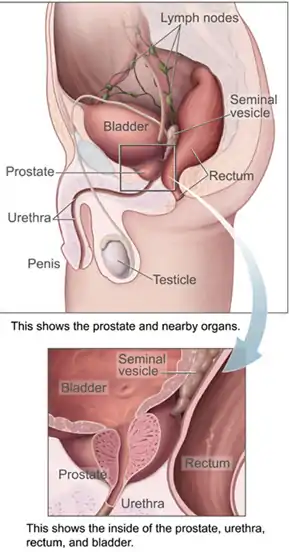

The prostate is both an accessory gland of the male reproductive system and a muscle driven mechanical switch between urination and ejaculation. It is found only in some mammals. It differs between species anatomically, chemically, and physiologically. Anatomically, the prostate is found below the bladder, with the urethra passing through it. It is described in gross anatomy as consisting of lobes, and in microanatomy by zone. It is surrounded by an elastic, fibromuscular capsule and contains glandular tissue as well as connective tissue.

The prostate is a gland of the male reproductive system. In adults, it is about the size of a walnut,[1] and has an average weight of about 11 grams, usually ranging between 7 and 16 grams.[2] The prostate is located in the pelvis. It sits below the urinary bladder and surrounds the urethra. The part of the urethra passing through it is called the prostatic urethra, which joins with the two ejaculatory ducts.[1] The prostate is covered in a surface called the prostatic capsule or prostatic fascia.[3]

The "lobe" classification describes lobes that, whilst originally defined in the foetus, are also visible in gross anatomy, including dissection and when viewed endoscopically.[4][3] The five lobes are the anterior lobe or isthmus; the posterior lobe; the right and left lateral lobes, and the middle or median lobe.